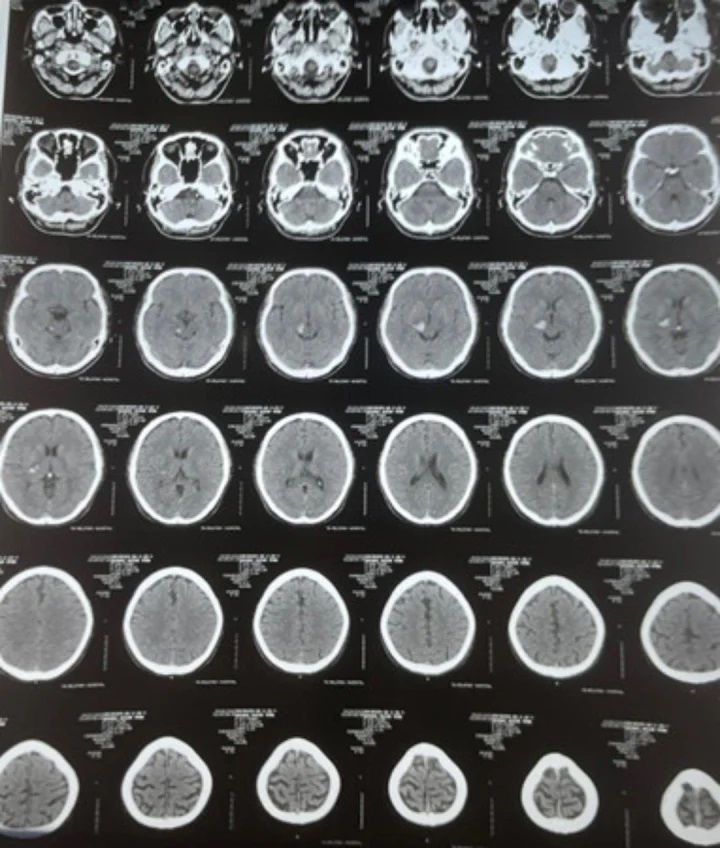

Phim chụp CT của bệnh nhân Nguyễn Văn Anh, 35 tuổi, ngụ quận 8, TP.HCM. Ảnh: BVCC.

Bệnh nhân có thể trạng béo phì, cao huyết áp, rối loạn lipid máu không điều trị thường xuyên, được các bác sĩ Bệnh viện Quân y 7A, TP.HCM thăm khám và chụp CT sọ não chẩn đoán xuất huyết khối não đồi thị phải.

"Lúc 22h, bệnh nhân xuất hiện các triệu chứng đau đầu, chóng mặt, tê và yếu nửa người trái, khoảng 22h30 đã được người nhà đưa đi cấp cứu kịp thời. Tại bệnh viện, các bác sĩ tiến hành điều trị tích cực, kiểm soát tốt huyết áp, đường huyết, nhiệt độ, để lại di chứng là tê bì nhẹ ở tay trái", BS Mạnh Hà nói.